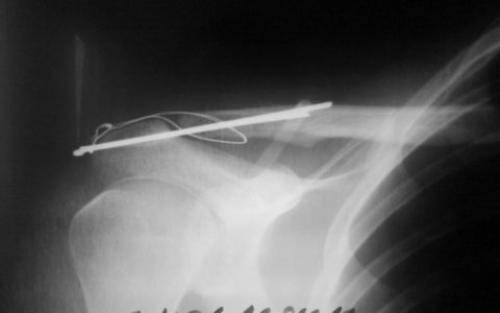

Фиксация ключицы спицами при остеосинтезе

Соединение отломков спицами

Спицами проводят остеосинтез ключицы с целью соединения фрагментов кости при переломе довольно редко, поскольку после операции они мигрируют, изгибаются и ломаются.